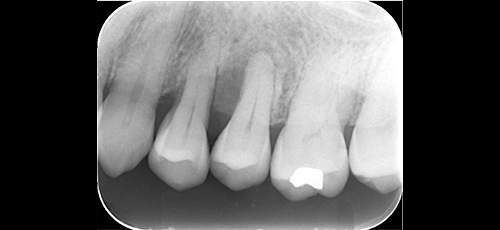

Case.1

治療後